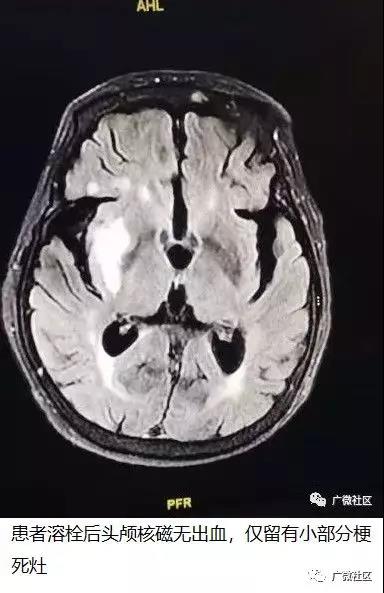

家住内蒙古自治区包头市昆都仑区恩和小区的88岁老人郭女士,2019年8月20日晚20:00在家准备去厕所时,突发言语不清,左侧肢体无力,不能活动,同时伴有头晕,恶心,呕吐,双眼向右侧凝视,逐渐嗜睡。家人急打120把老人送到包头医学院第一附属医院急诊科,急查头颅CT无出血,于22:05分收入神经内科三病区病房。神经内科三病区主任刘丹,根据患者症状及检查,诊断为急性脑梗死。患者当时发病不足3小时,理论上可以给予静脉溶栓治疗,但患者高龄,使用静脉溶栓伴随出血风险极高。这种情况在临床治疗中非常棘手:如果不溶栓,患者重则危及生命,轻则必定遗留后遗症,偏瘫卧床,生活不能自理;如果溶栓,则有可能出现脑出血等风险,同样有可能危及生命,遗留后遗症。在这左右为难的时候,刘丹主任综合分析了患者发病特点、发病时间、个体特征等多方面因素,当机立断,指示:建议溶栓。在与家属沟通后,家属表示完全理解,相信刘丹主任的专业判断,愿意承担风险,遵从建议,同意静脉溶栓治疗。早在一旁准备的医护人员,立即给予患者静脉溶栓治疗,此时距患者发病仅2.5小时。溶栓过程顺利,2小时后,患者神志清醒,精神良好,左下肢可抬起,左上肢可在床上挪动。此时已是凌晨1点,全科医护人员轮班值守,彻夜未眠,刘丹主任多次指示,评估患者疗效,拟定下一步治疗方案。次日清晨(8月21日上午6时左右),老人症状基本缓解,言语功能明显好转,左侧肢体趋于正常,高兴地说:“谢谢大夫,我的左手左脚能动了,都能下地行走了,好多了,我们小区有几个老年人,得了脑梗,都落下后遗症,生活都不能自理,我比他们都幸运!”看着老人手舞足蹈的样子,大家都相顾莞尔,一夜的辛劳都倍感值得。